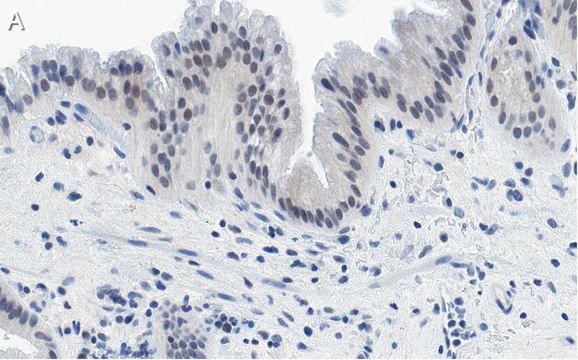

Immunohistochemistry (Paraffin) Analysis: A 1:100 dilution from a representative lot detected Nrf2 in human gallbladder and human cervical cancer tissue sections.